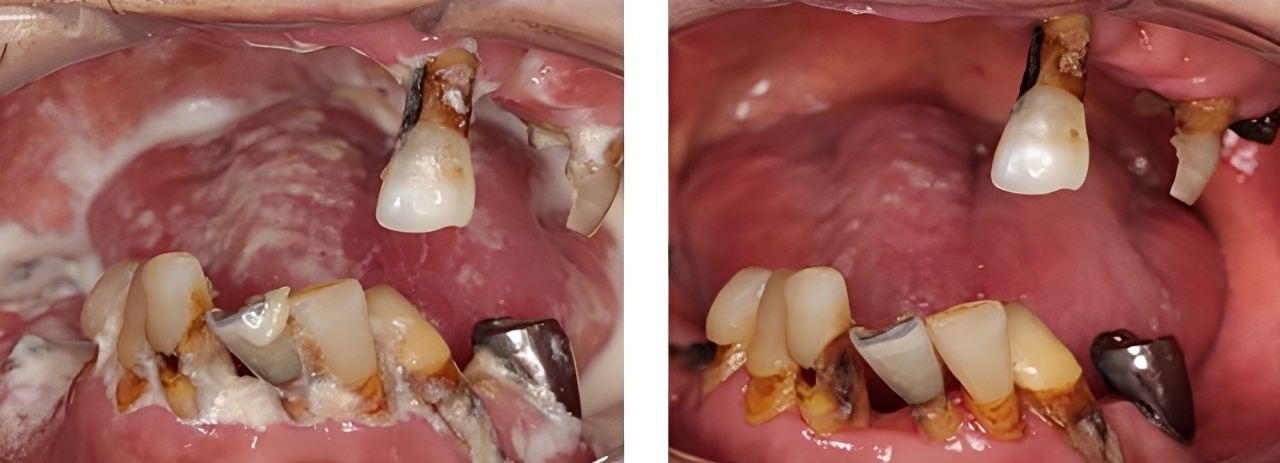

全顎保険治療

術前

術後

| 治療内容 | 全顎的に保険内で治療を行った |

|---|---|

| 治療期間・回数 | 約2.5年・約50回 |

| 費用 | 保険適用となります |

| リスク・副作用 |

| 治療内容 | 全顎的に咬合再構成を行い保険内で治療を行った |

| 治療期間・回数 | 約4年・約50回 |